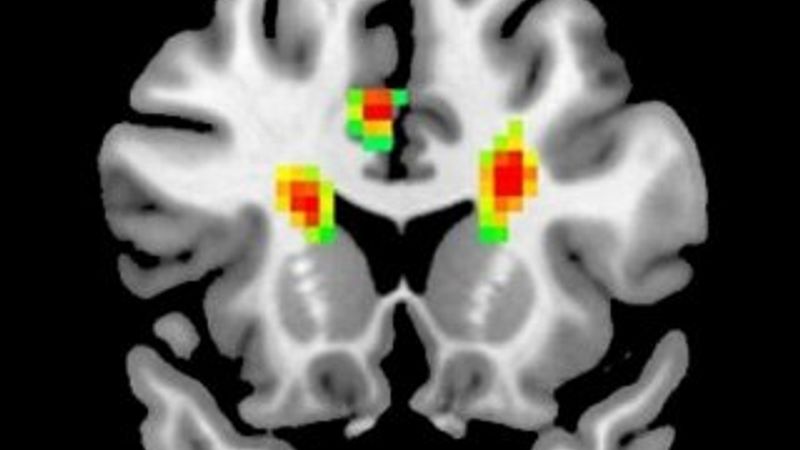

Aşık insanların beyin MR'ı çekildi(Aşık olan bir insanın beyni)

Araştırma sonucuna göre, aşıkken beynimize giden kan miktarı artıyor ve beynimizin 12 bölgesi aktif oluyor. Beynin önde gelen fonksiyonel değişiklikleriyle ilgili ilk amfirik kanıtını gözler önüne seren araştırma, aşkın insanlar üzerindeki etkilerini tam olarak açıklığa kavuşturmasa da işe bir yerlerden başlıyor.